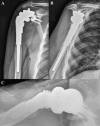

Case presentation: We report a case of a 70-year-old male with periosteal chondrosarcoma of the proximal humerus who underwent margin-negative resection and reverse total shoulder endoprosthetic reconstruction that was complicated by glenosphere dissociation sustained from falling onto a hyperflexed arm. Successful revision arthroplasty was performed.

Conclusion: Enhancing glenohumeral joint stability after wide resection of the proximal humerus is important to address rotator cuff insufficiency. The greater levering effect of a longer humeral prosthesis used to increase soft tissue tension may also increase the risk of glenosphere dissociation secondary to trauma. Proper soft-tissue tensioning and surgical technique are critical.